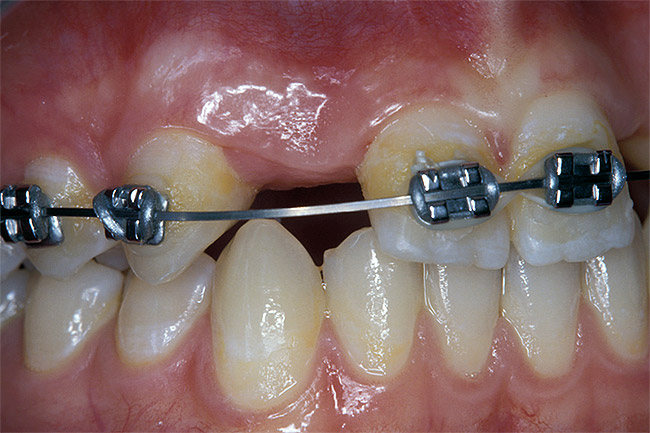

Before the day of surgery, the patient was seen by the orthodontist for the removal of the orthodontic brackets. The patient still was not pleased with the position of the two centrals, and it was determined that this would be addressed after implant placement (Figure 13A). The anatomical variations of the crestal tissue and lack of interdental papilla can be appreciated in the close-up views of the right and left sites (Figure 13B and 13C). There were no surprises on the day of surgery as all of the decisions were made during the planning phase, before the scalpel ever touched the patient. The occlusal view of the CT 3D model revealed the wider alveolar ridge on the right side and thinner crest on the left side (Figure 14A). This was confirmed when the full thickness mucoperiosteal flaps were elevated, and the underyling bone revealed (Figure 14B). The tooth-borne templates were designed to facilitate the drills and drilling sequence specific to the diameters of the predetermined implants (Figure 15A). Each template contained an embedded 5-mm long stainless steel tube, which was approximately 0.2-mm wider than each drill (just wide enough to allow for the drills to rotate freely). Once positioned over the natural teeth, the template was secure and offered precision accuracy in transferring the implant locations from the original software-designed plan, allowing the potential for internal and external irrigation (Figure 15B). The 3.7-mm diameter Tapered Screw-Vent implant drilling sequence requires three drills: pilot, intermediate, and final sizing. Thus, three separate templates were fabricated to a.commodate these sizes. The templates were removed easily and replaced with the next sequential size in less time than it takes to change the drill on the surgical handpiece. After the osteotomies had been.completed, the implants were delivered to the site (Figure 16A and Figure 16B). For this internal hex connection implant, the author r.commends that the flat of the antirotational hex be positioned to the facial for proper orientation of the restorative.components (Figure 17A). Preprepared margins were created from a milled titanium fixture mount transfer post, which was delivered to the implant as support for an immediate transitional restoration. The facial “dot” helped confirm the orientation of the abutment to the facially positioned flat side of the internal hex connection (Figure 17B). Before cementation of the transitional acrylic restorations, a closed-tray, fixture-level impression was made, and a soft-tissue model fabricated.

Figure 13a  Before implant surgery, the orthodontic brackets were removed, revealing (A) the position of the centrals, and (B, C) the anatomical variations of the crestal tissue and lack of interdental papilla.

Figure 13a

Figure 13b  Before implant surgery, the orthodontic brackets were removed, revealing (A) the position of the centrals, and (B, C) the anatomical variations of the crestal tissue and lack of interdental papilla.

Figure 13b